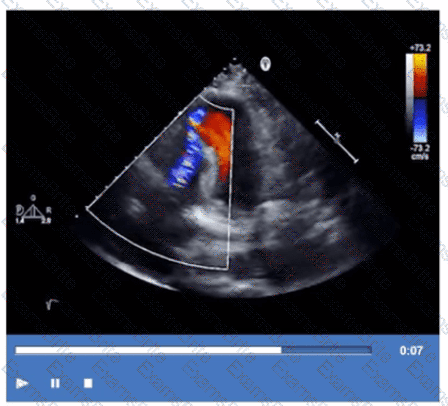

Which coronary artery territory is associated with the wall motion abnormality demonstrated in this video?